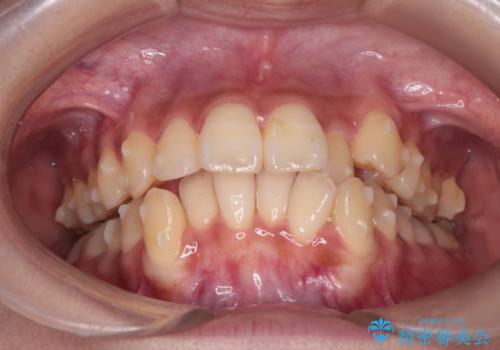

反対咬合を治したい。インビザライン

- 前歯の反対咬合を治したいことを主訴に来院されました。

インビザラインにて臼歯の遠心移動を行いながら、スペースを作り反対咬合を改善することができました。

反対咬合はインビザラインの方が治しやすい場合もあります。